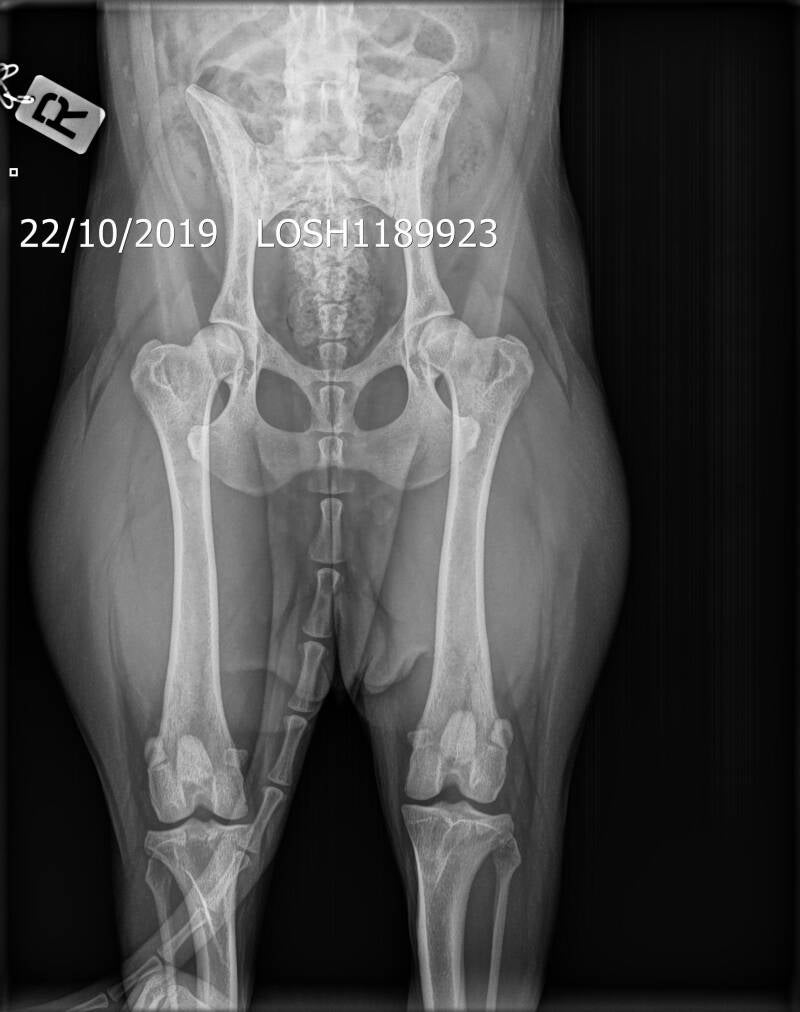

Q-Mo of Kaliko's home